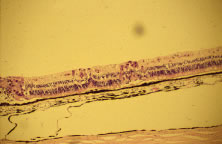

Light microscopic examination of these retinas reveals full-thickness necrosis and loss of the retinal architecture.25,30,35 Within the necrotic retina, macrophages, plasma cells, and other inflammatory cells are found in addition to cells containing eosinophilic inclusions. There is a sharp demarcation between affected and nonaffected retina, suggesting cell-to-cell transmission of the virus. Arteritis manifests as endothelial cell swelling with occlusion of the vessel lumen, infiltration of the subendothelium with plasma cells, and inflammatory cell thrombi. When healing occurs, a thin glial scar replaces the necrotic neural elements. Herpesvirus capsids may be observed in electron microscopic specimens of actively infected retinal tissue but are not seen once healing has occurred and glial scar tissue replaces the necrotic retina.28,30